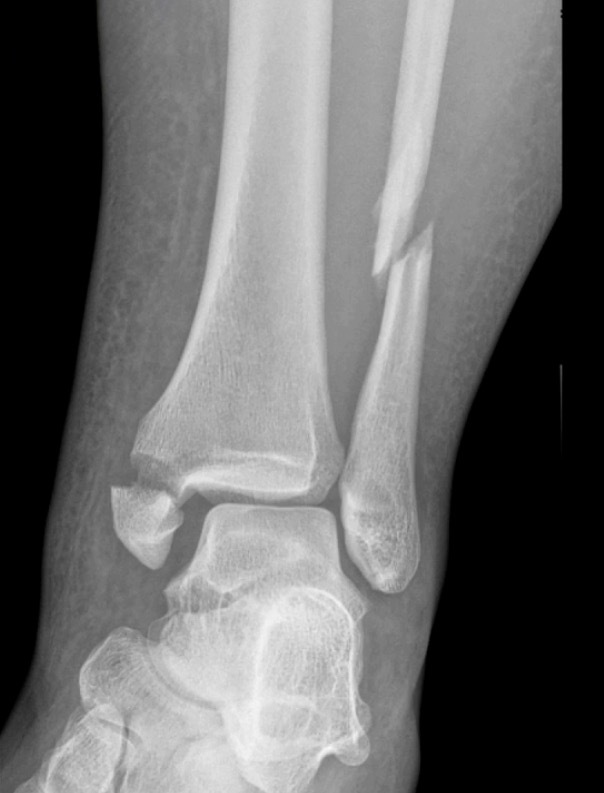

Now, what about ankle fractures with syndesmosis injuries?

Our Randomized Controlled Trial specifically excluded those, because when I was a resident, syndesmosis injury was kept non-weight-bearing for three months, that was the standard (three months in a cast). Unfortunately, the treatment is sometimes worse than the disease. There is much controversy in terms of weight bearing for syndesmosis injuries, and not as much evidence on this specific injury compared to previously discussed ankle fractures. Figure 7 is a type of fracture we’re referring to: After you fix it, what do you do next?

A small RCT (Khaleel M, et al. Foot Ankle Orthop. 2024;9(4)) was conducted assessing syndesmosis injuries comparing early versus delayed weight-bearing. They had a relatively small sample size: only 16 patients in one group, 23 in the other group, but they did show that there was potential improvement in range of motion with the early group, and there was no catastrophic failure. This raises an interesting question: “can we allow early weightbearing after syndesmosis fixation?”, and we need more studies on this specific topic.